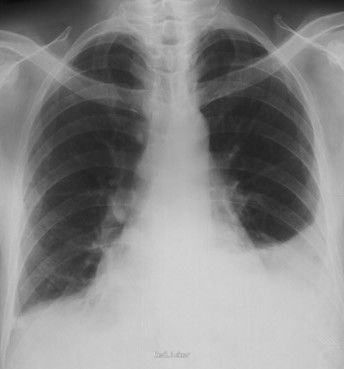

T 39.2℃,R 58次/min,P 160次/min,BP 125/76mmHg,血氧饱和度0.88。躯干皮肤可见密集红色斑疹,压之退色。呼吸困难。左侧肋间隙较右侧饱满,双肺均可闻及中、细湿性啰音,无胸膜摩擦音。心率 160次/min,律齐,肢端暖,毛细血管充盈时间 3s。 床边心电图示窦性心动过速。胸片示左下肺感染,左侧胸腔积液;血常规示WBC 4.66×10^9/L,N 0.92,PLT 213×109/L。凝血功能:凝血酶原时间 17.8s。心肌酶无异常。

入院给予经鼻无创持续气道正压通气,补液,亚胺培南西司他丁联合万古霉素抗感染,丙种球蛋白冲击支持,甲基泼尼松龙抗炎等治疗;同时行左侧胸腔穿刺术抽得30ml脓液送检。患儿病情进行性加重,入院后约6h出现心跳骤停,抢救无效死亡。血培养第2d回报为化脓性链球菌(A组β溶血性链球菌)阳性。最后诊断为:1.链球菌中毒休克综合征;2.急性支气管肺炎;3.左侧胸腔积液。